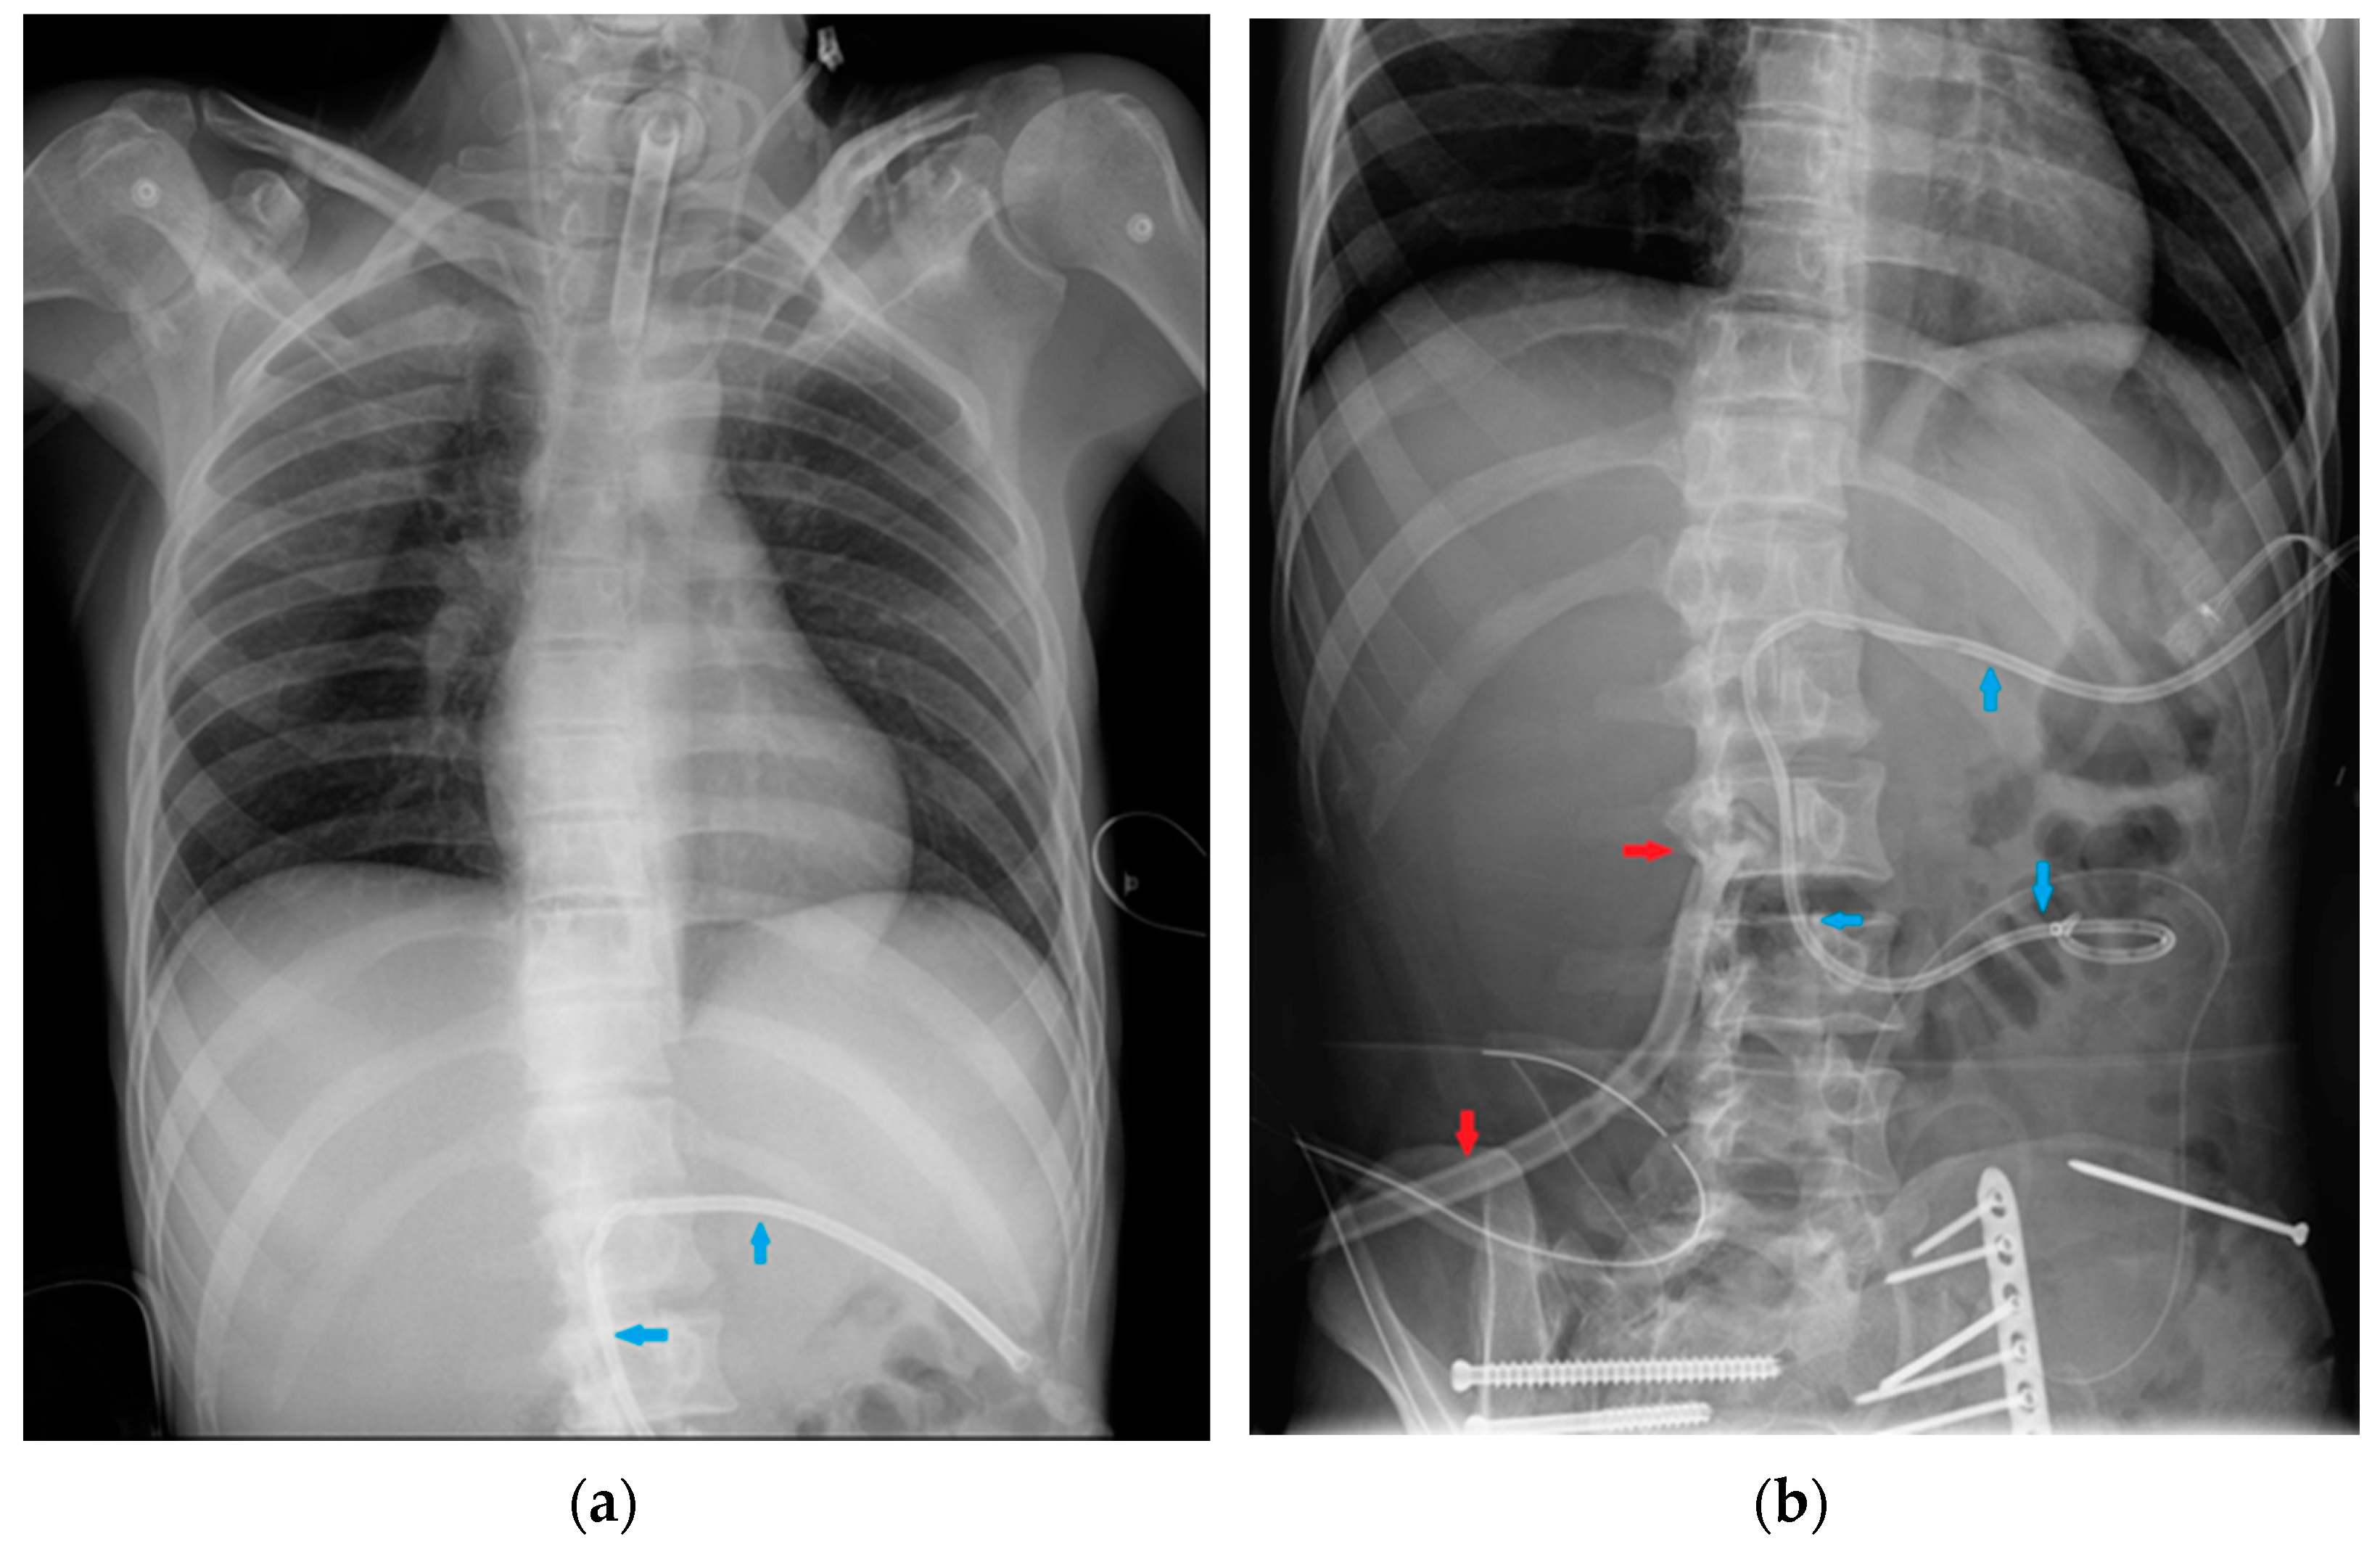

Figure 31.

Image of a pig-tail chest tube inserted through the right lateral chest wall draining a right basal pulmonary effusion. Note that in this case, the lateral view (b) depicts the tube loops more clearly than PA view (a); also, there seems to be an effect given by the uplifting of the arms in the lateral view, with the insertion point of the tube being dragged upward and so “emphasizing” its looping appearance.